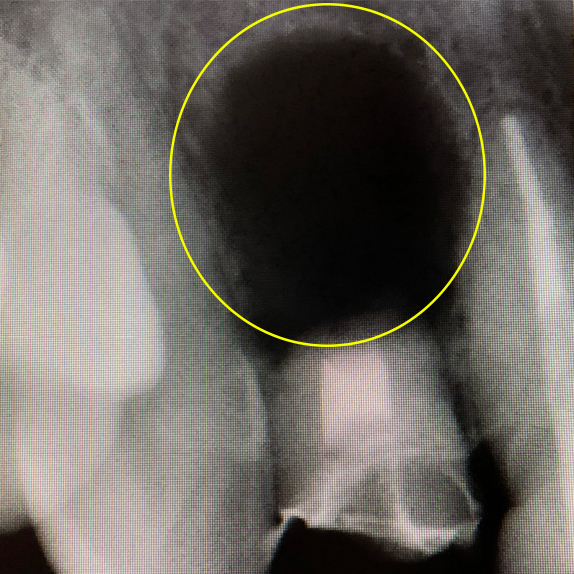

CASE 07 マイクロエンド(精密根管治療)+歯根周囲掻爬(歯周外科)

歯ぐきがよく腫れる主訴で来院。レントゲン写真の術前を見ると大きな影が確認できます。この部分に嚢胞(のうほう)がある状態です。マイクロエンドと歯根周囲掻爬(歯周外科)をすることで改善したケースです。